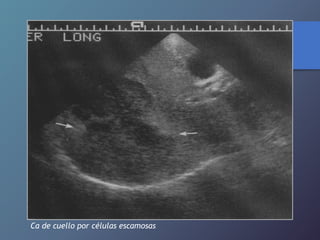

Ca de cuello por células escamosas

Ca de cuellopor células escamosas